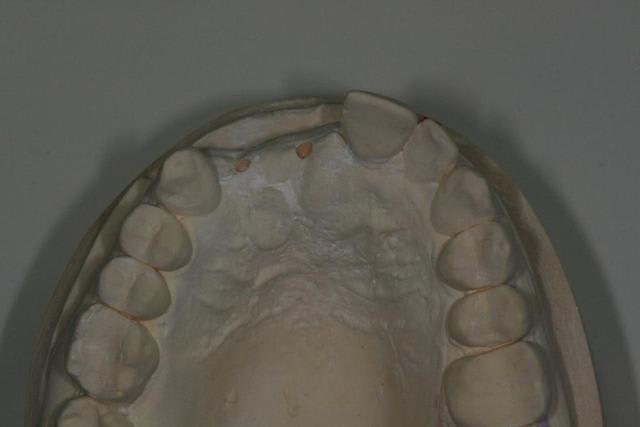

tu devrais faire faire par ton prothésiste un wax avec les dents en blanc et les tissus mous qu'il te manque en rouge afin de bien visualiser tous les tissus qu'il te manque.

Bon voila le scann de 11-12 (pas 21-22 comme noté)

C'est vrai que j'ai à mort d'os en épaisseur.

Le manque est surtout en hauteur.

Dans tous les cas je refais 21 en même temps.

le montage guide RX laisse supposer un manque d'un mm en 12 et ok en 11. Surcomble en cj pour en éliminer au cas où avant les empreintes